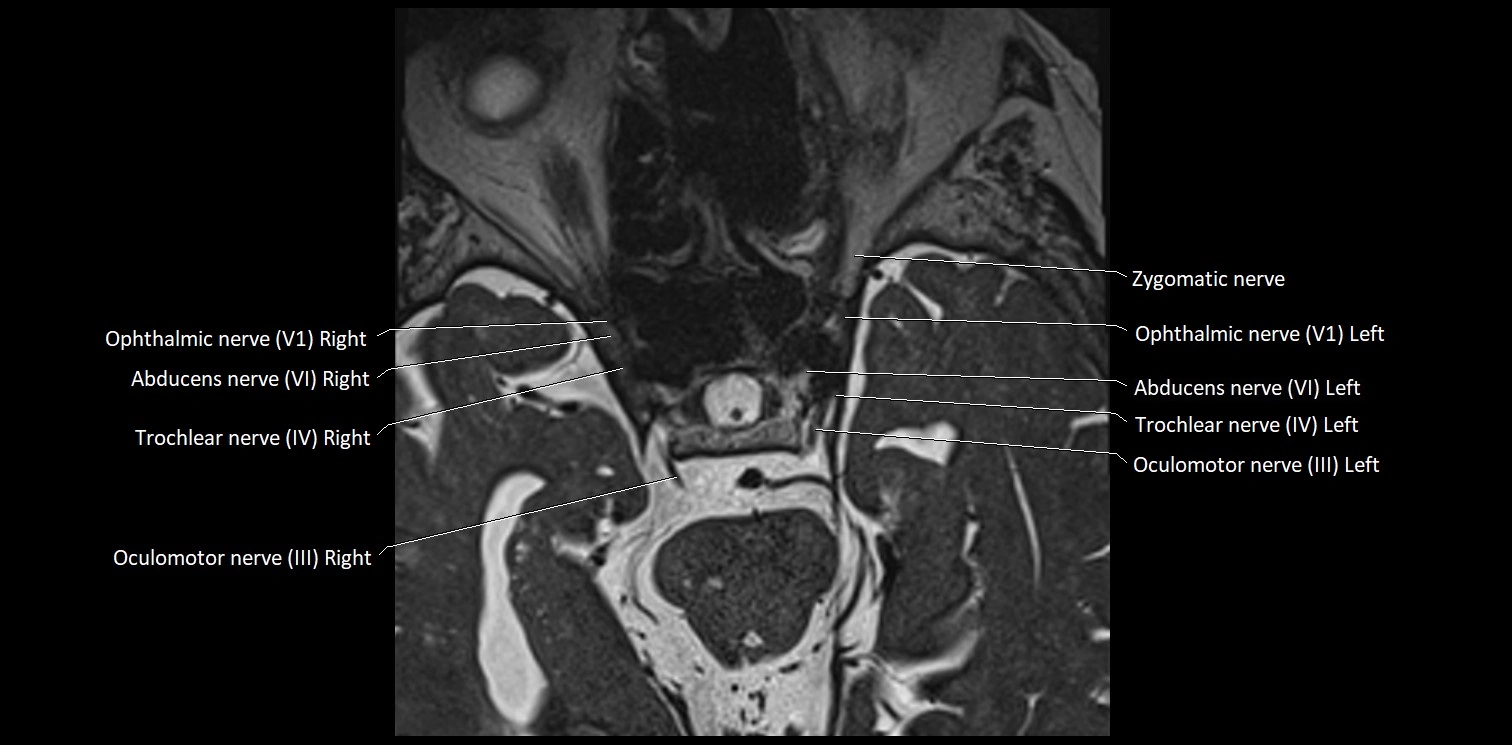

MRI images

image